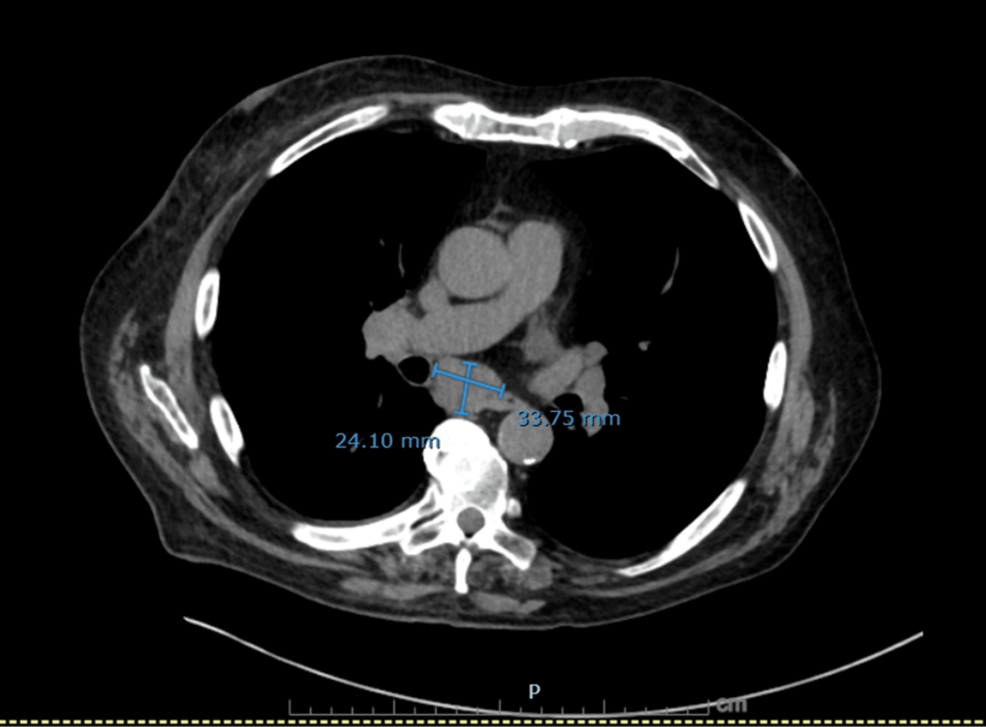

Figure 4: Axial non-contrast CT chest showing markedly enlarged subcarinal lymph node

A dominant subcarinal lymph node measuring 24 × 34 mm, highly suspicious for malignant mediastinal involvement.